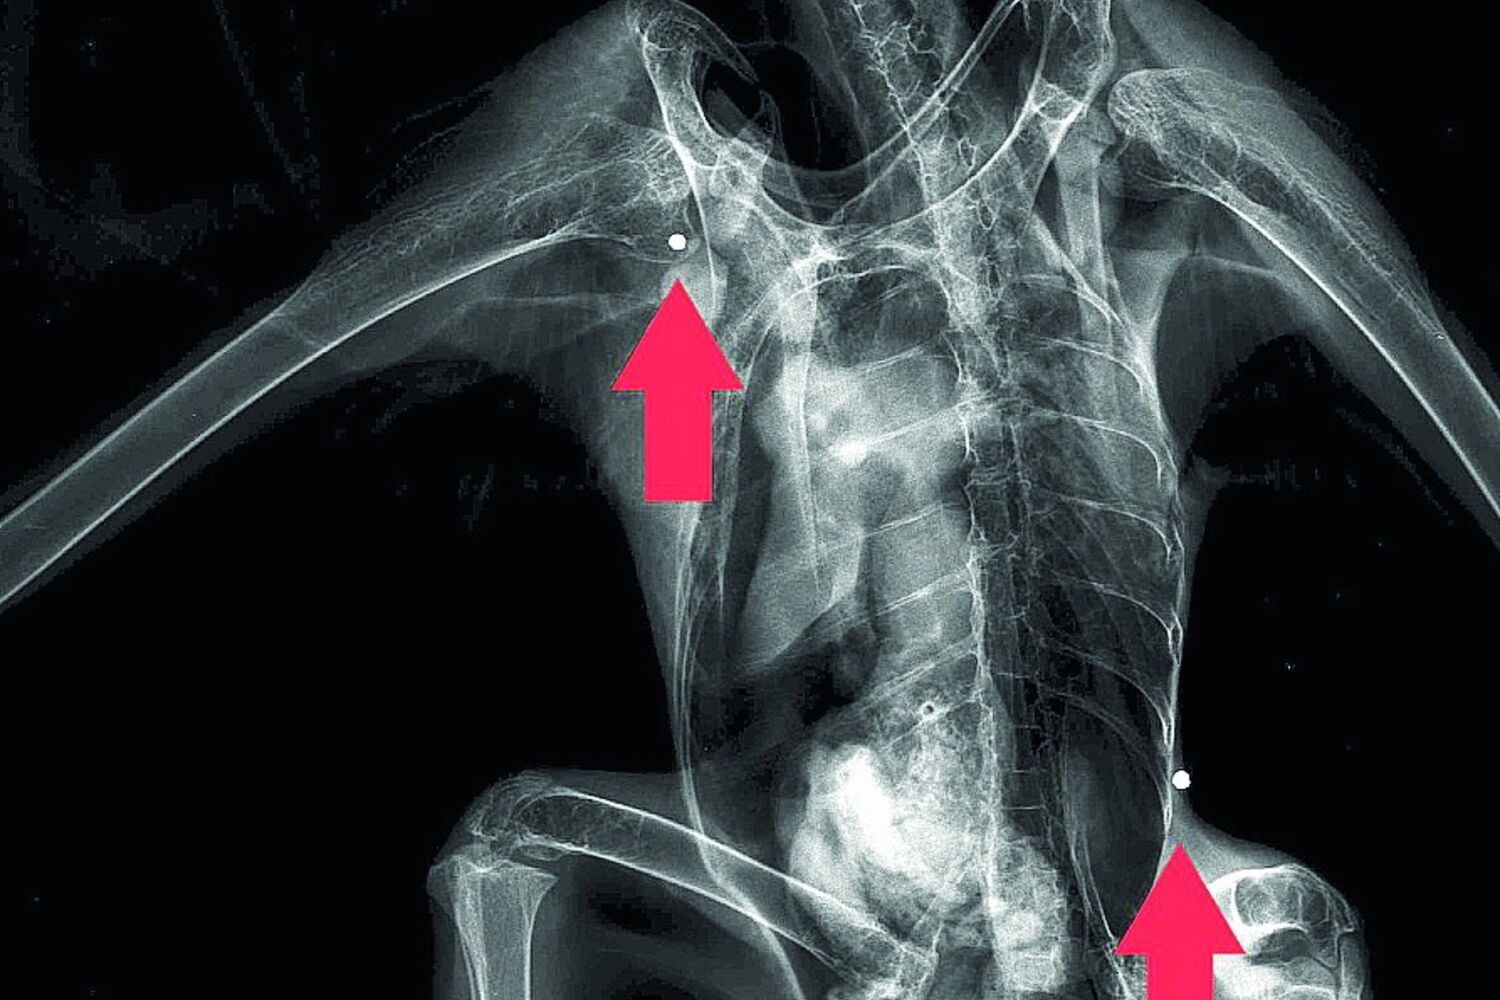

Ave ficou ferida após ser atingida com tiros de caçadeira.

A águia, que tem o estatuto de ‘Quase Ameaçada’ em Portugal, terá sido alvejada também no Alentejo, em meados de agosto. Foi encontrada em Moura e depois levada para o RIAS. No centro, o exame radiológico detetou três projéteis de caçadeira: na cabeça, ombro direito e costado esquerdo. Foram ainda descobertos restos de um quarto projétil.

"Foi possível retirar um dos projéteis, mas os restantes não puderam ser extraídos por questões médicas", explica o RIAS. Foi colocada uma ligadura na asa da águia, que ficou numa câmara de recuperação interior, onde foi mantida sob vigilância constante.